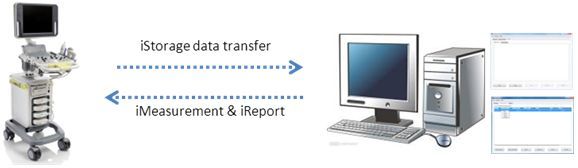

iStorageTM?/ iMeasurementTM?/ iReportTM

iStorage: –Ω–µ–ø–æ—Å—Ä–µ–¥—Å—Ç–≤–µ–Ω–Ω–∞—è –ø–µ—Ä–µ–¥–∞—á–∞ –∏–∑–æ–±—Ä–∞–∂–µ–Ω–∏–π –∏ –æ—Ç—á–µ—Ç–æ–≤ –Ω–∞ –ü–ö –ø–æ —Å–µ—Ç–µ–≤–æ–º—É –∫–∞–±–µ–ª—é.

iMeasurement & iReport: –ø—Ä–æ–≥—Ä–∞–º–º–Ω–æ–µ –æ–±–µ—Å–ø–µ—á–µ–Ω–∏–µ –¥–ª—è –ü–ö, —Ä–∞–±–æ—Ç–∞—é—â–µ–µ –≤ –æ—Ñ—Ñ–ª–∞–π–Ω-—Ä–µ–∂–∏–º–µ, –¥–ª—è —Ä–∞–±–æ—Ç—ã —Å –∑–∞–¥–∞–Ω–Ω–æ–π –ø–æ–ª—å–∑–æ–≤–∞—Ç–µ–ª–µ–º —Ç–∞–±–ª–∏—Ü–æ–π –∏–∑–º–µ—Ä–µ–Ω–∏–π, —Ñ–æ—Ä–º—É–ª–∞–º–∏ —Ä–∞—Å—á–µ—Ç–∞ –∏ —à–∞–±–ª–æ–Ω–∞–º–∏ –æ—Ç—á–µ—Ç–∞.